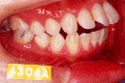

治療前後の比較

受け口

出っ歯

乱抗歯

開咬